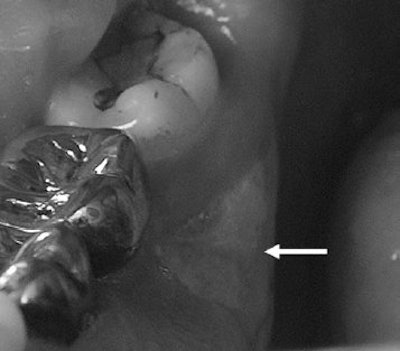

![]() |

| A 61-year-old man with metastatic prostate cancer treated with zoledronate presents with painful bone exposure of the right mandible (arrow). Phal PM, Myall RWT, Assael LA, Weissman JL, "Imaging Findings of Bisphosphonate-Associated Osteonecrosis of the Jaws," American Journal of Neuroradiology, Vol. 28:6, pp 1139-1145. © American Society of Neuroradiology. |

Phal is from the department of radiology at Royal Melbourne Hospital in Australia; his co-authors are from the departments of oral and maxillofacial surgery, otolaryngology, and ophthalmology, as well as the School of Dentistry at Oregon Health & Science University in Portland.

In this retrospective study, Phal's group included 15 patients on bisphosphonates who developed osteonecrosis of the jaws. Among the 11 female subjects, six had breast cancer, three had osteoporosis, and two had multiple myeloma. Among the four male patients, there were two cases of prostate cancer, one of multiple myeloma, and one of osteoporosis.